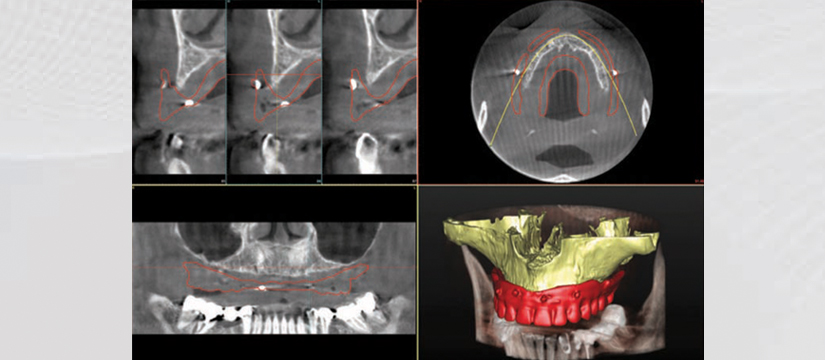

Our clinic pledges to offer you the best quality services with the latest technology equipments, such as OWANDY IMAX TOUCH CEPH. This amazing equipment provides high-definition images for an unmistakable diagnostication. OWANDY is the leader of dental imagery in France ,America ,Germany and more. The newest product OWANDY I-Max Touch 3D provides all the radiographic services in one device.

Equipped with 17 different programs ,it provides every clinical examination including:

- Panoramic View

- 3D Detntition Positioning

- 3D TMJ Left Positioning

- 3D TMJ Right Positioning

- 3D Sinus Positioning

- Cephalometric Examination